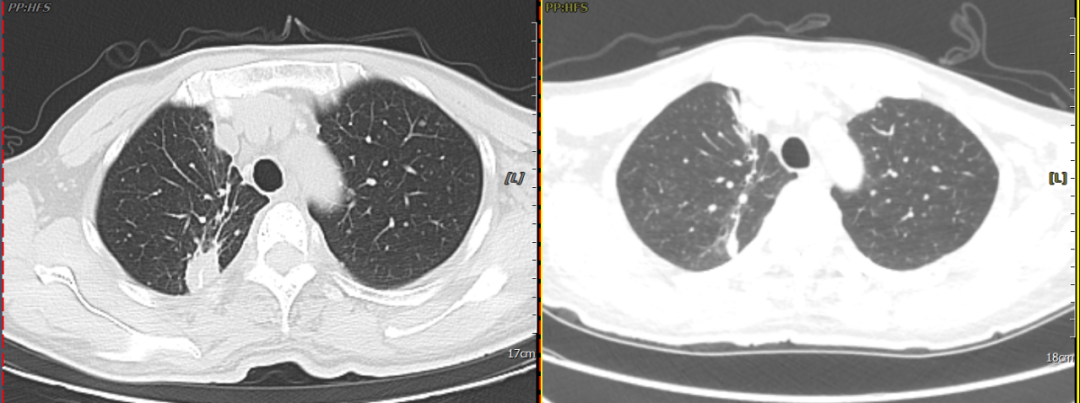

Patient Yan, male, 52 years old, presented with cough, expectoration, and discomfort in the left shoulder and upper limb. An enhanced chest CT performed at an external hospital revealed a nodule in the apical segment of the right lung. A biopsy of the mass in the apical-posterior segment of the right upper lobe was performed under thoracoscopy. Postoperative pathological diagnosis confirmed (lesion in the apical segment of the right upper lobe) invasive lung cancer. The patient subsequently sought treatment at our hospital. An enhanced cranial MRI performed in our department indicated brain metastatic carcinoma, and a whole-body ECT scan revealed multiple bone metastases. Combined genetic testing for lung cancer detected an L858R mutation. After oral targeted therapy, the patient's symptoms of cough, expectoration, and pain significantly improved. A follow-up chest CT showed a marked reduction in the tumor size in the right upper lobe, with a clinical efficacy evaluation of PR.